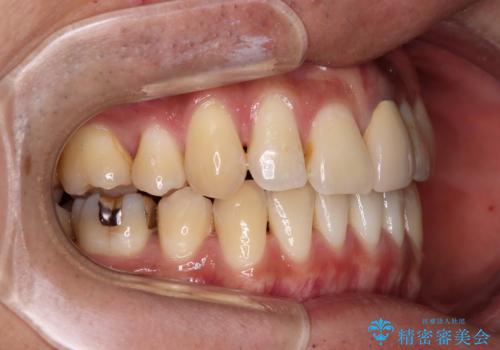

- 下顎の八重歯を気にして来院された患者様です。

左下以外、3本の第一小臼歯が既に抜去されており、左下は八重歯になっている状態でした。

左下の八重歯は手前に傾斜していたため、インビザラインによる抜歯矯正が可能と判断し、後方にある第一小臼歯を抜歯してインビザラインにて矯正治療を行うこととしました。

ワイヤー矯正と比較すると、八重歯が後方に傾斜した仕上がりとなりましたが、患者様ご希望のインビザラインにて十分な歯列を達成することができました。